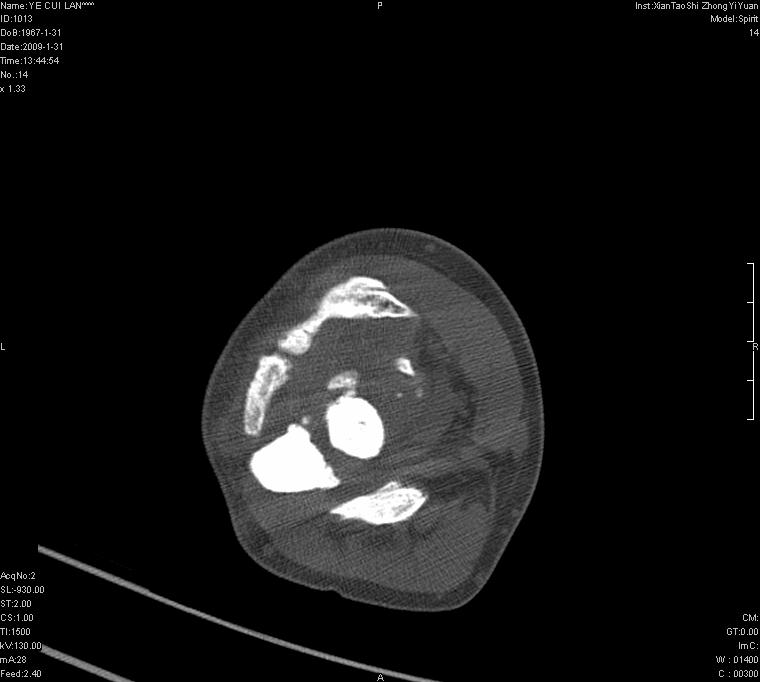

以下是引用王明发在2009-2-9 11:53:00的发言:[br]支持夏科氏关节,必要时行脊髓mri检查 [br]夏科氏关节是指由于某些神经系统疾病引起的关节病变,也被称为神经性关节炎。常见病因有脊髓痨、脊髓空洞症等。原发的神经病变可以造成关节深部感觉障碍,对于关节的震荡、磨损、挤压、劳倦不能察觉因而也不能自主地保护和避免,而神经营养障碍又可使修复能力低下,使病人在无感觉状态下造成了关节软骨的磨损和破坏,关节囊和韧带松弛无力,易形成关节脱位和连枷关节。关节面的破坏和骨赘的脱落变成关节内游离体。关节外形饱满肿胀,内有出血和渗出。这种病早期并无疼痛,不易被病人重视,仅表现为关节肿胀、无力、活动过度、动摇不稳。关节肿胀、无痛、活动范围超常是本病的重要特征。x光片可见有关节骨端广泛破坏、硬化或呈奇异形态,骨赘形成,关节间隙不规则或增宽,周围软组织钙化、关节内游离体、骨碎片等。结合x光片及临床症状,病人又有神经系统原发病症,即可确诊

以下是引用hhcckk在2009-2-9 14:31:00的发言:[br]夏科关节的六大表现[br]1.关节软组织肿胀。[br]2.关节的脱位与半脱位。[br]3.关节内的游离体。[br]4.关节面硬化,新骨形成。[br]5.骨质萎缩与破坏。[br]6.关节结构的紊乱。[br]加上患者无明显疼痛,诊断的把握性比较大